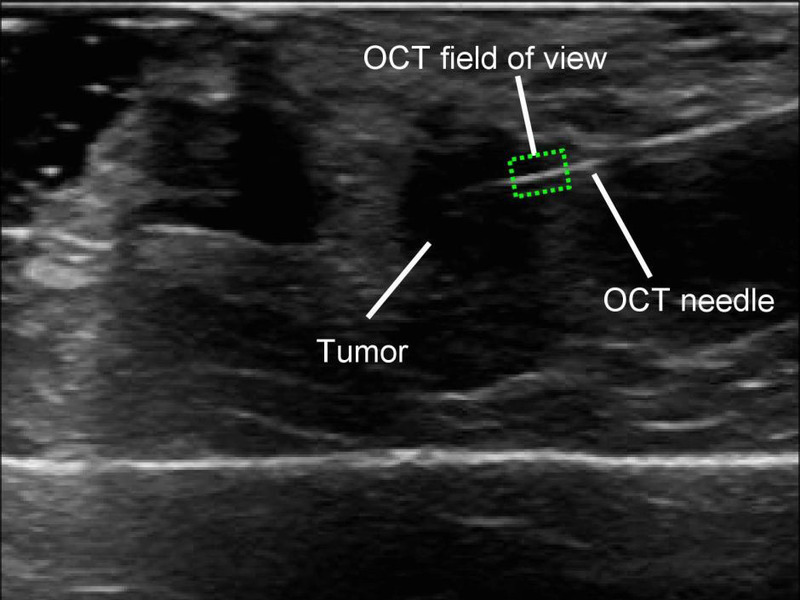

The microscope itself is getting tinier and tinier. Scientists at the University of Western Australia have recently produced the world’s smallest microscope -- so small, it fits inside a needle. The scope is less than a third of a millimeter wide.

Photo: Courtesy of the University of Western Australia. Needle Microscope.

This represents a major breakthrough because it enables surgeons to detect cancer cells missed during operations to remove tumors. Professor Christobel Saunders, a surgeon and breast cancer specialist says, “We really can see at a microscopic level where there is tumour. So it’s almost like an ultrasound picture, but at a microscopic level.”

Trials are expected within two years. Needle scopes could become commonplace around the world within a decade.